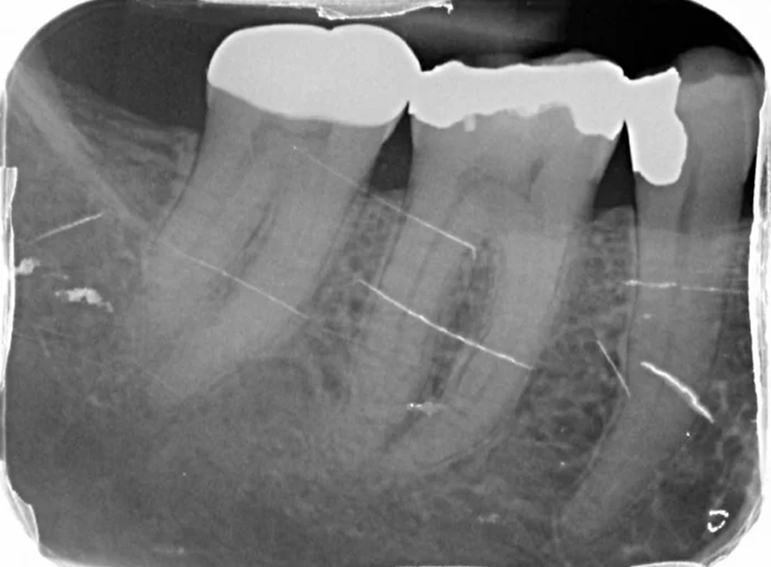

Crown lengthening surgery and adhesive onlay on a molar.